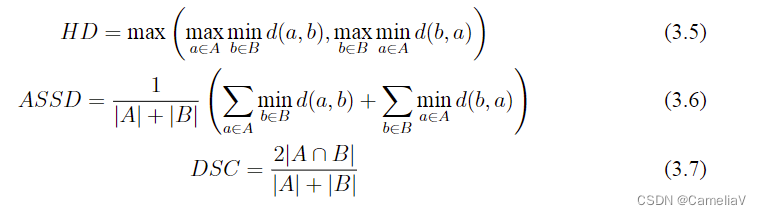

公式

可以参考知网上的论文,把公式截图放置bing等可以识别图片的llm中,要求通过latex实现公式,对照截图小修小改即可。公式引用用\eqref。

\begin{equation}\label{hd}

HD = \max \left( \max_{a\in A} \min_{b\in B} d(a, b), \max_{b\in B} \min_{a\in A} d(b, a) \right)

\end{equation}

\begin{equation}\label{assd}

ASSD = \frac{1}{|A| + |B|} \left( \sum_{a\in A} \min_{b\in B} d(a, b) + \sum_{b\in B} \min_{a\in A} d(b, a) \right)

\end{equation}

\begin{equation}\label{dsc}

DSC = \frac{2|A \cap B|}{|A| + |B|}

\end{equation}